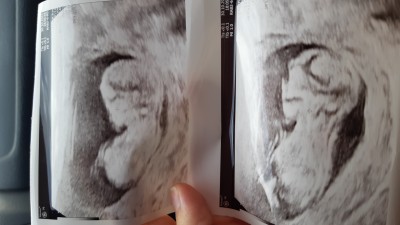

Kızlar  gittik bugün kendini gostrmedi  ya direk arkasına döndü snra doktorlar vurdu karnma döndü bacak arasında kordon var dedi kalp atışı 145 dedi bna tahminde bulunabilirmsnz?image

13+3 haftalık cnm

Çenesi sivri. Benim bebeşiminde öyleydi sivriydi erkek... Kesin sizinkide erkek.. Yinede herşeyin hayırlısı tabi